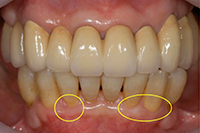

歯の根が露出して部分の歯ぐきが再生。